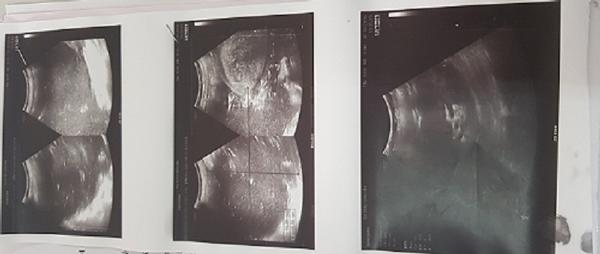

Sau khi thăm khám, hình ảnh siêu âm cho thấy dịch khu trú ổ bụng chưa loại trừ khối kích thước 198 x 130mm. Hình ảnh chụp cắt lớp cho thấy vùng hạ vị xuất hiện khối kích thước 17,5 x 23,6 x 24,1cm tỷ trọng dịch đặc trong có dịch khí với thành mỏng, khối choán chỗ trong tiểu khung và ổ bụng. Sau hội chẩn bệnh viện Ths.BSCK2. Đỗ Khắc Huỳnh chỉ định mổ lấy khối dịch.

Hình ảnh siêu âm của bệnh nhân.